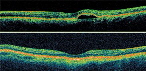

• Glaucoma anterior segment assessment and GAT - Wendy Newsom- • OCT Interpretation and advice for AMD - Aneela Raja